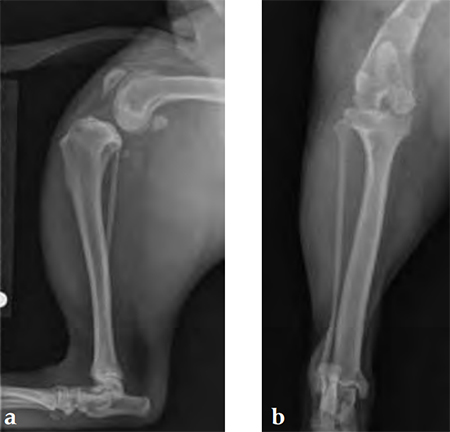

Case 1: English bulldog

(Case provided by Brian Beale, Houston, USA)

A 4-year-old, female, spayed, 33 kg English bulldog had a CrCL tear and a medial patellar luxation. The small stature 3.5 mm TPLO plate was perfect for this dog due to the small profile of the bone and the need to use a heavier plate (3.5 vs a 2.7 mm). In the past, veterinary surgeons have been forced to either squeeze the standard TPLO 3.5 mm plate on the bone or use an undersized TPLO 2.7 mm plate. In this patient, the shorter and smaller profile head of the small stature TPLO 3.5 mm was perfect.